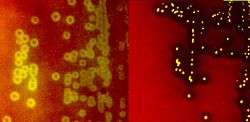

Species of Streptococcus are classified based on their hemolytic properties.[6] Alpha-hemolytic species cause oxidization of iron in hemoglobin molecules within red blood cells, giving it a greenish color on blood agar. Beta-hemolytic species cause complete rupture of red blood cells. On blood agar, this appears as wide areas clear of blood cells surrounding bacterial colonies. Gamma-hemolytic species cause no hemolysis.

When alpha hemolysis (α-hemolysis) is present, the agar under the colony is dark and greenish. Streptococcus pneumoniae and a group of oral streptococci (Streptococcus viridans or viridans streptococci) display alpha hemolysis. This is sometimes called green hemolysis because of the color change in the agar. Other synonymous terms are incomplete hemolysis and partial hemolysis. Alpha hemolysis is caused by hydrogen peroxide produced by the bacterium, oxidizing hemoglobin to green methemoglobin.

Beta hemolysis (β-hemolysis), sometimes called complete hemolysis, is a complete lysis of red cells in the media around and under the colonies: the area appears lightened (yellow) and transparent. Streptolysin, an exotoxin, is the enzyme produced by the bacteria which causes the complete lysis of red blood cells. There are two types of streptolysin: Streptolysin O (SLO) and streptolysin S (SLS). Streptolysin O is an oxygen-sensitive cytotoxin, secreted by most Group A streptococcus (GAS), and interacts with cholesterol in the membrane of eukaryotic cells (mainly red and white blood cells, macrophages, and platelets), and usually results in β-hemolysis under the surface of blood agar. Streptolysin S is an oxygen-stable cytotoxin also produced by most GAS strains which results in clearing on the surface of blood agar. SLS affects immune cells, including polymorphonuclear leukocytes and lymphocytes, and is thought to prevent the host immune system from clearing infection. Streptococcus pyogenes, or group A Streptococcus (GAS), displays beta hemolysis.

Alpha-hemolytic S. viridans (right) and beta-hemolytic S. pyogenes (left) streptococci growing on blood agar